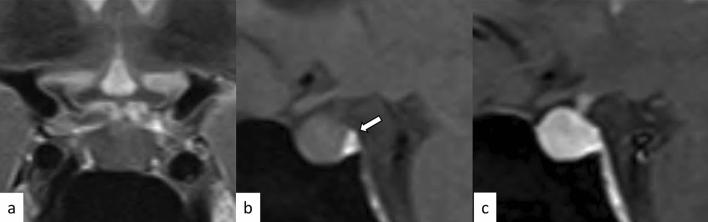

垂体炎的神经影像学:病因和影像模拟。

Neuroimaging of hypophysitis: etiologies and imaging mimics.

Hypophysitis is an inflammatory disease affecting the pituitary gland. Hypophysitis can be classified into multiple types depending on the mechanisms (primary or secondary), histology (lymphocytic, granulomatous, xanthomatous, plasmacytic/IgG4 related, necrotizing, or mixed), and anatomy (adenohypophysitis, infundibulo-neurohypophysitis, or panhypophysitis). An appropriate diagnosis is vital for managing these potentially life-threatening conditions. However, physiological morphological alterations, remnants, and neoplastic and non-neoplastic lesions may masquerade as hypophysitis, both clinically and radiologically. Neuroimaging, as well as imaging findings of other sites of the body, plays a pivotal role in diagnosis. In this article, we will review the types of hypophysitis and summarize clinical and imaging features of both hypophysitis and its mimickers.

垂体炎是一种影响垂体的炎症性疾病。根据发病机制(原发性或继发性)、组织学(淋巴细胞性、肉芽肿性、含铁血黄素沉积性、浆细胞/IgG4 相关性、坏死性或混合性)和解剖学(腺垂体炎、漏斗神经垂体炎或全垂体炎),垂体炎可分为多种类型。适当的诊断对于治疗这些潜在危及生命的疾病至关重要。然而,生理形态改变、残留物以及肿瘤性和非肿瘤性病变可能在临床上和影像学上表现为垂体炎。神经影像学以及身体其他部位的影像学表现对诊断起着关键作用。本文将回顾垂体炎的类型,并总结垂体炎及其类似物的临床和影像学特征。